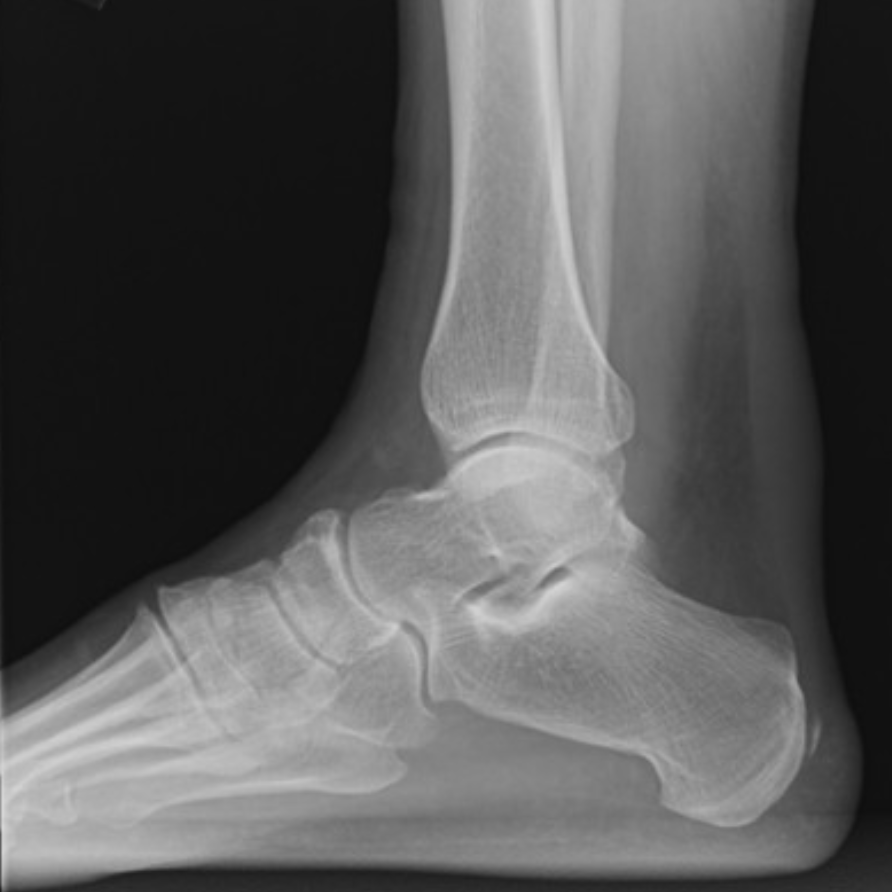

Ankle

Haglund Deformity

• Bony overgrowth of the posterior-superior calcaneous

• Associated with high heel wearing